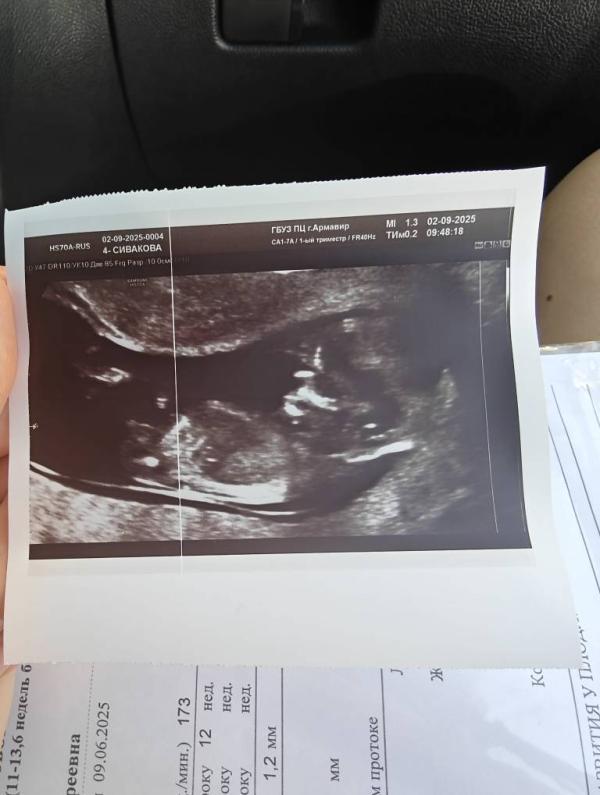

Первый скрининг при беременности: как прошло УЗИ и впечатления

1 скрининг сделали 👌🏻

По УЗИ все хорошо